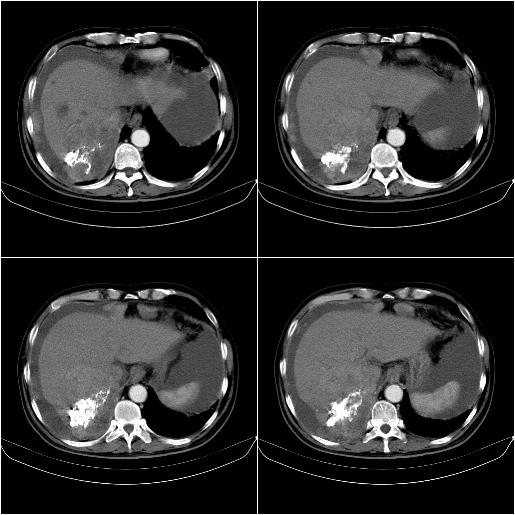

标题: CT21651:M,67Y,肝癌9月,介入术后3月。

m,67y,肝癌9月,介入术后3月。现腹胀、纳差、腹泻。

1)肝癌介入治疗术后碘油沉积不良。2)门静脉瘤栓形成,腹膜广泛性转移。3)肝硬化,脾大,腹水。4)慢性胆囊炎。